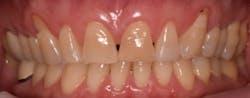

This new biological approach involving blood derivatives A-PRF and I-PRF combined with precision minimally invasive surgery for root coverage demonstrates faster healing without the need of a donor site. The morbidity of GDT is decreased and patient case acceptance is higher compared with traditional grafts. Before-and-after pictures are shown below (figures 15–22).